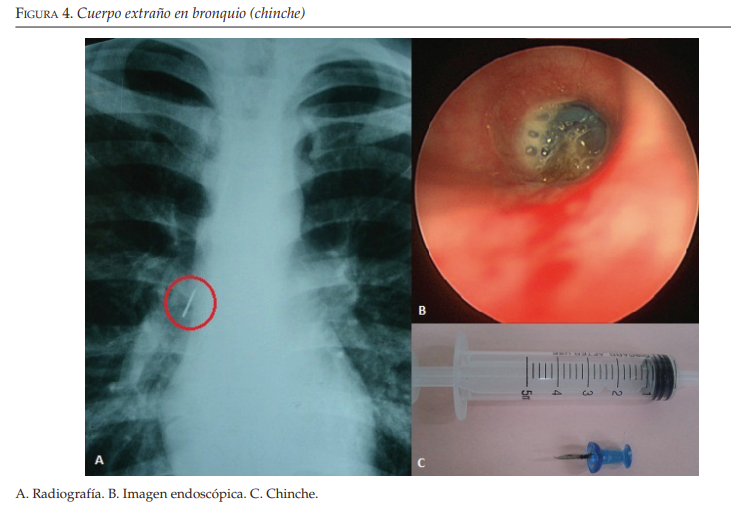

- La obstrucción de la vía aérea inferior (tráquea intratorácica , bronquios principales) puede deberse a cuerpos extraños, tumores, estenosis laringeas

postraqueostomía o intubaciones prolongadas, estenosis bronquiales.